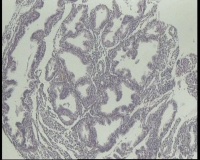

| 图片: | |

- 急!请老师看看34岁子宫内膜

| 性别 | 女 | 年龄 | 34岁 | 临床诊断 | 子宫内膜息肉? |

| 一般病史 | 末次月经:11月20日,近两个月无诱因性生活有阴道少许血性分泌物 | ||||

| 标本名称 | 宫内容物 | ||||

| 大体所见 | 膜样碎组织3.0厘米 | ||||